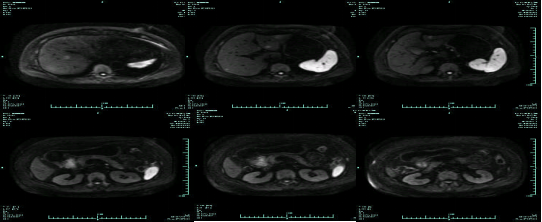

• MR示:

MR-H1